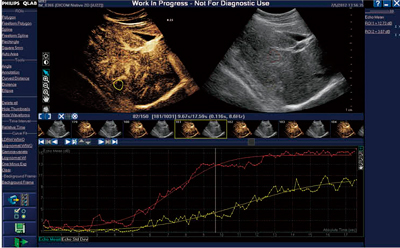

●定量解析法:ROI解析(QLAB software)(図3)

Time Intensity Curve(TIC)

造影超音波画像の定量解析でポピュラーな方法の1つに,経時的輝度回復曲線(time intensity curve:TIC)を求める方法がある。QLABのROI機能を用いることで,造影直後に装置上で簡単にTICを表示可能である。さらに,動きによる補正(Motion Compensation)が可能で,患者さんに負担をかけることなく再現性の良い解析が可能である。種々のカーブフィッティングにも対応しており,さまざまなニーズに合わせた近似曲線の表示が可能である。

図3 TIC定量解析